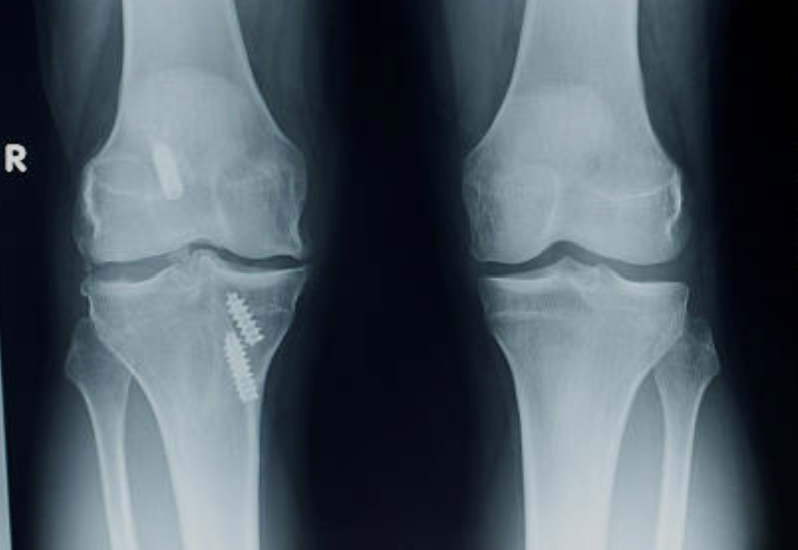

십자인대 파열 증상 원인 치료방법 등 십자인대 파열에 관한 정보 알아보도록 하겠습니다. 십자인대는 무릎 관절 내부에 있는 크로스밴드로, 대퇴골과 정강이 사이를 가로지르며 무릎 관절을 유지하는 중요한 역할을 합니다. 하지만 외상이나 나이, 비만 등으로 인해 손상되면 무릎 통증, 불안정성, 굽힘 및 펴짐 제한 등의 증상이 나타납니다. 큰 부상이 없어도 반복적인 무릎 부하나 체중 등에 의해 부담을 받는 경우에도 손상이 생길 수 있으며, 무릎 관절을 지지하는 인대 중에서는 가장 높은 부상률을 가지고 있습니다. 처치하지 않으면 불안정한 무릎 관절이 발생하며, 장기적으로는 무릎 관절염이나 연골손상 등을 초래할 수 있기 때문에 증상이 나타나면 적절한 치료가 필요합니다.

십자인대는 무릎 관절을 안정시키는 중요한 조직 중 하나로, 만일 십자인대가 파열된다면 무릎을 움직이는데 큰 문제가 발생할 수 있습니다. 십자인대 파열의 초기 증상으로는 무릎 부위에 갑작스러운 통증이 느껴지는 경우가 많습니다. 이어서 부종이나 출혈, 무릎 관절 부근 부분의 압력감 또한 느껴질 수 있습니다. 걷거나 달리는 등 일상적인 활동이 어려워지며, 무릎 관절 근육이 약해져 근육 긴장도나 균형감각 또한 떨어지는 경우가 있습니다. 만약 십자인대 파열이 심한 경우, 무릎 관절이 불안정해져 엉덩이나 무릎 부상의 위험성이 높아질 수 있습니다. 이로 인해 무릎 관절이 불균형하게 움직이면서 연골이 마모되고 골관절염 등의 문제가 발생할 가능성이 높아집니다.

1. 수술: 십자인대 파열이 심각한 경우 수술이 필요합니다. 수술 방법은 파열의 위치, 크기 및 환자의 개인 상황에 따라 달라집니다. 대표적인 수술 방법으로는 십자인대 재건술, 십자인대 대체술 등이 있습니다.